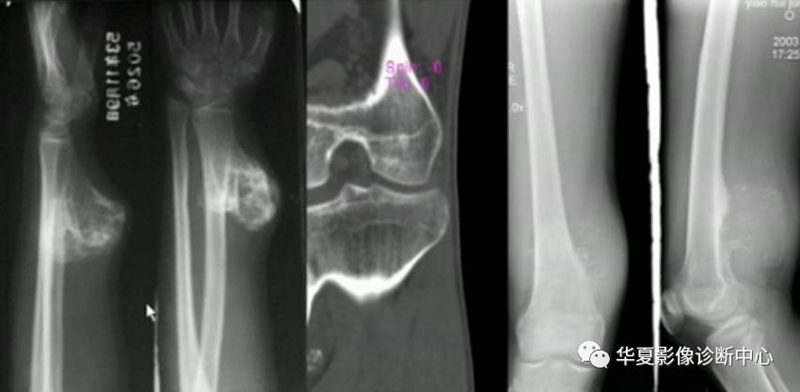

形态:环状,弧状,点状具有诊断意义,大小,良性者形态完整,境界清楚,密度均匀。恶性者相反。(如下图)

骨质增生,骨膜反应,良性者边续,局限,清楚,厚在2mm以上,恶性者间断,相对广泛。

骨样骨瘤良性骨膜反应,骨肉瘤恶性骨膜反应